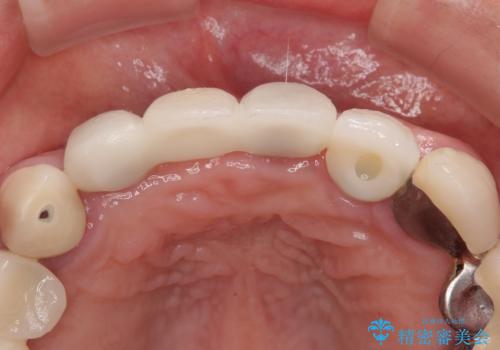

初回カウンセリング時にはセラミッククラウンが装着されていましたが、インプラント治療でのご来院時には前歯は外れて紛失をしてしまったとのことでした。

事前に仮歯の型取りをして用意をしていたため、インプラント埋入後に速やかに仮歯を装着しました。

インプラントの安定度も高く、抜歯と埋入から2か月後にはオールセラミッククラウンを装着することができました。